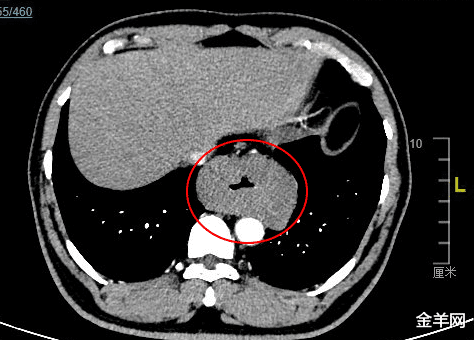

治疗前 , 杨浩贤主任医师为古先生安排了全面细致的术前检查 。 胸腹部CT检查结果提示 , 食管胸下段管壁不均匀环形增厚 , 最厚处达42mm , 长约81mm , 与胸主动脉相贴;超声胃镜检查确认了在距离门齿约35-40cm处 , 可见食管近全周粘膜下隆起肿物 , 表面粘膜光滑 , 起源于食管固有肌层 , 累及食管全周 , 病情非常复杂 。

CT图像显示肿瘤环绕食管全周 , 压迫食管腔 , 肿瘤长径达8cm